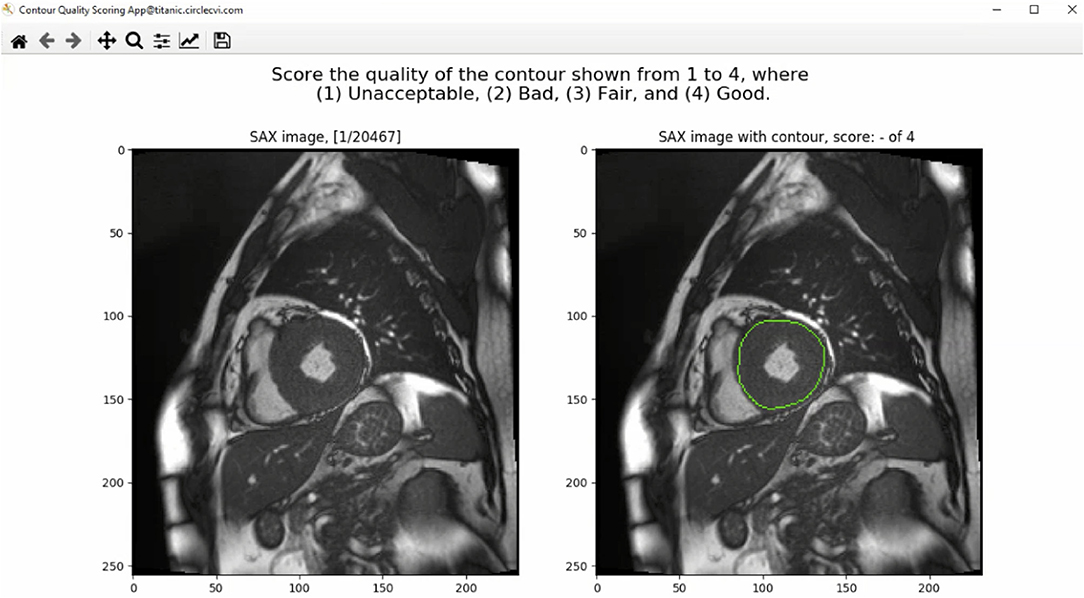

A contour quality scoring application was developed to input clinician's feedback on both manual and automated contours obtained from the same images. The application was composed of a graphical user interface (GUI) to display contoured images and offered user interactivity to rapidly parse through the data and input user's feedback on the quality of the presented contours.

The GUI of the contour quality scoring tool is shown in Figure 1. From the dataset constructed with both manual and corresponding automated contours, the application selected a case randomly to present to the user and expected a quality score from a predefined rubric. The left panel of the GUI showed a SAX image with the corresponding index of the image out of the total number of images available in the database. The right panel, instead, showed the same image with an overlaid contour to which the user was asked to assign a quality score. Once the user inputed the score, arrow keys on the keyboard were used to advance to the next available image in the database.

Figure 1. The graphical user interface (GUI) of the contour quality scoring tool. The left panel shows the current SAX image. The right panel shows the same image with overlaid contour to which the rater is asked to assign a quality score. The title above the right panel shows a blank quality score, which will be updated when a value is entered by the user.

The source of the contour was not shown to the user to avoid causing any unwanted bias in the rating of the contours. In addition, multiple annotations for each image were displayed separately to receive quality rating for each contour type individually. The process continued until the user rated all cases available in the dataset, resulting in ratings received for both source of contours for each image in the dataset.